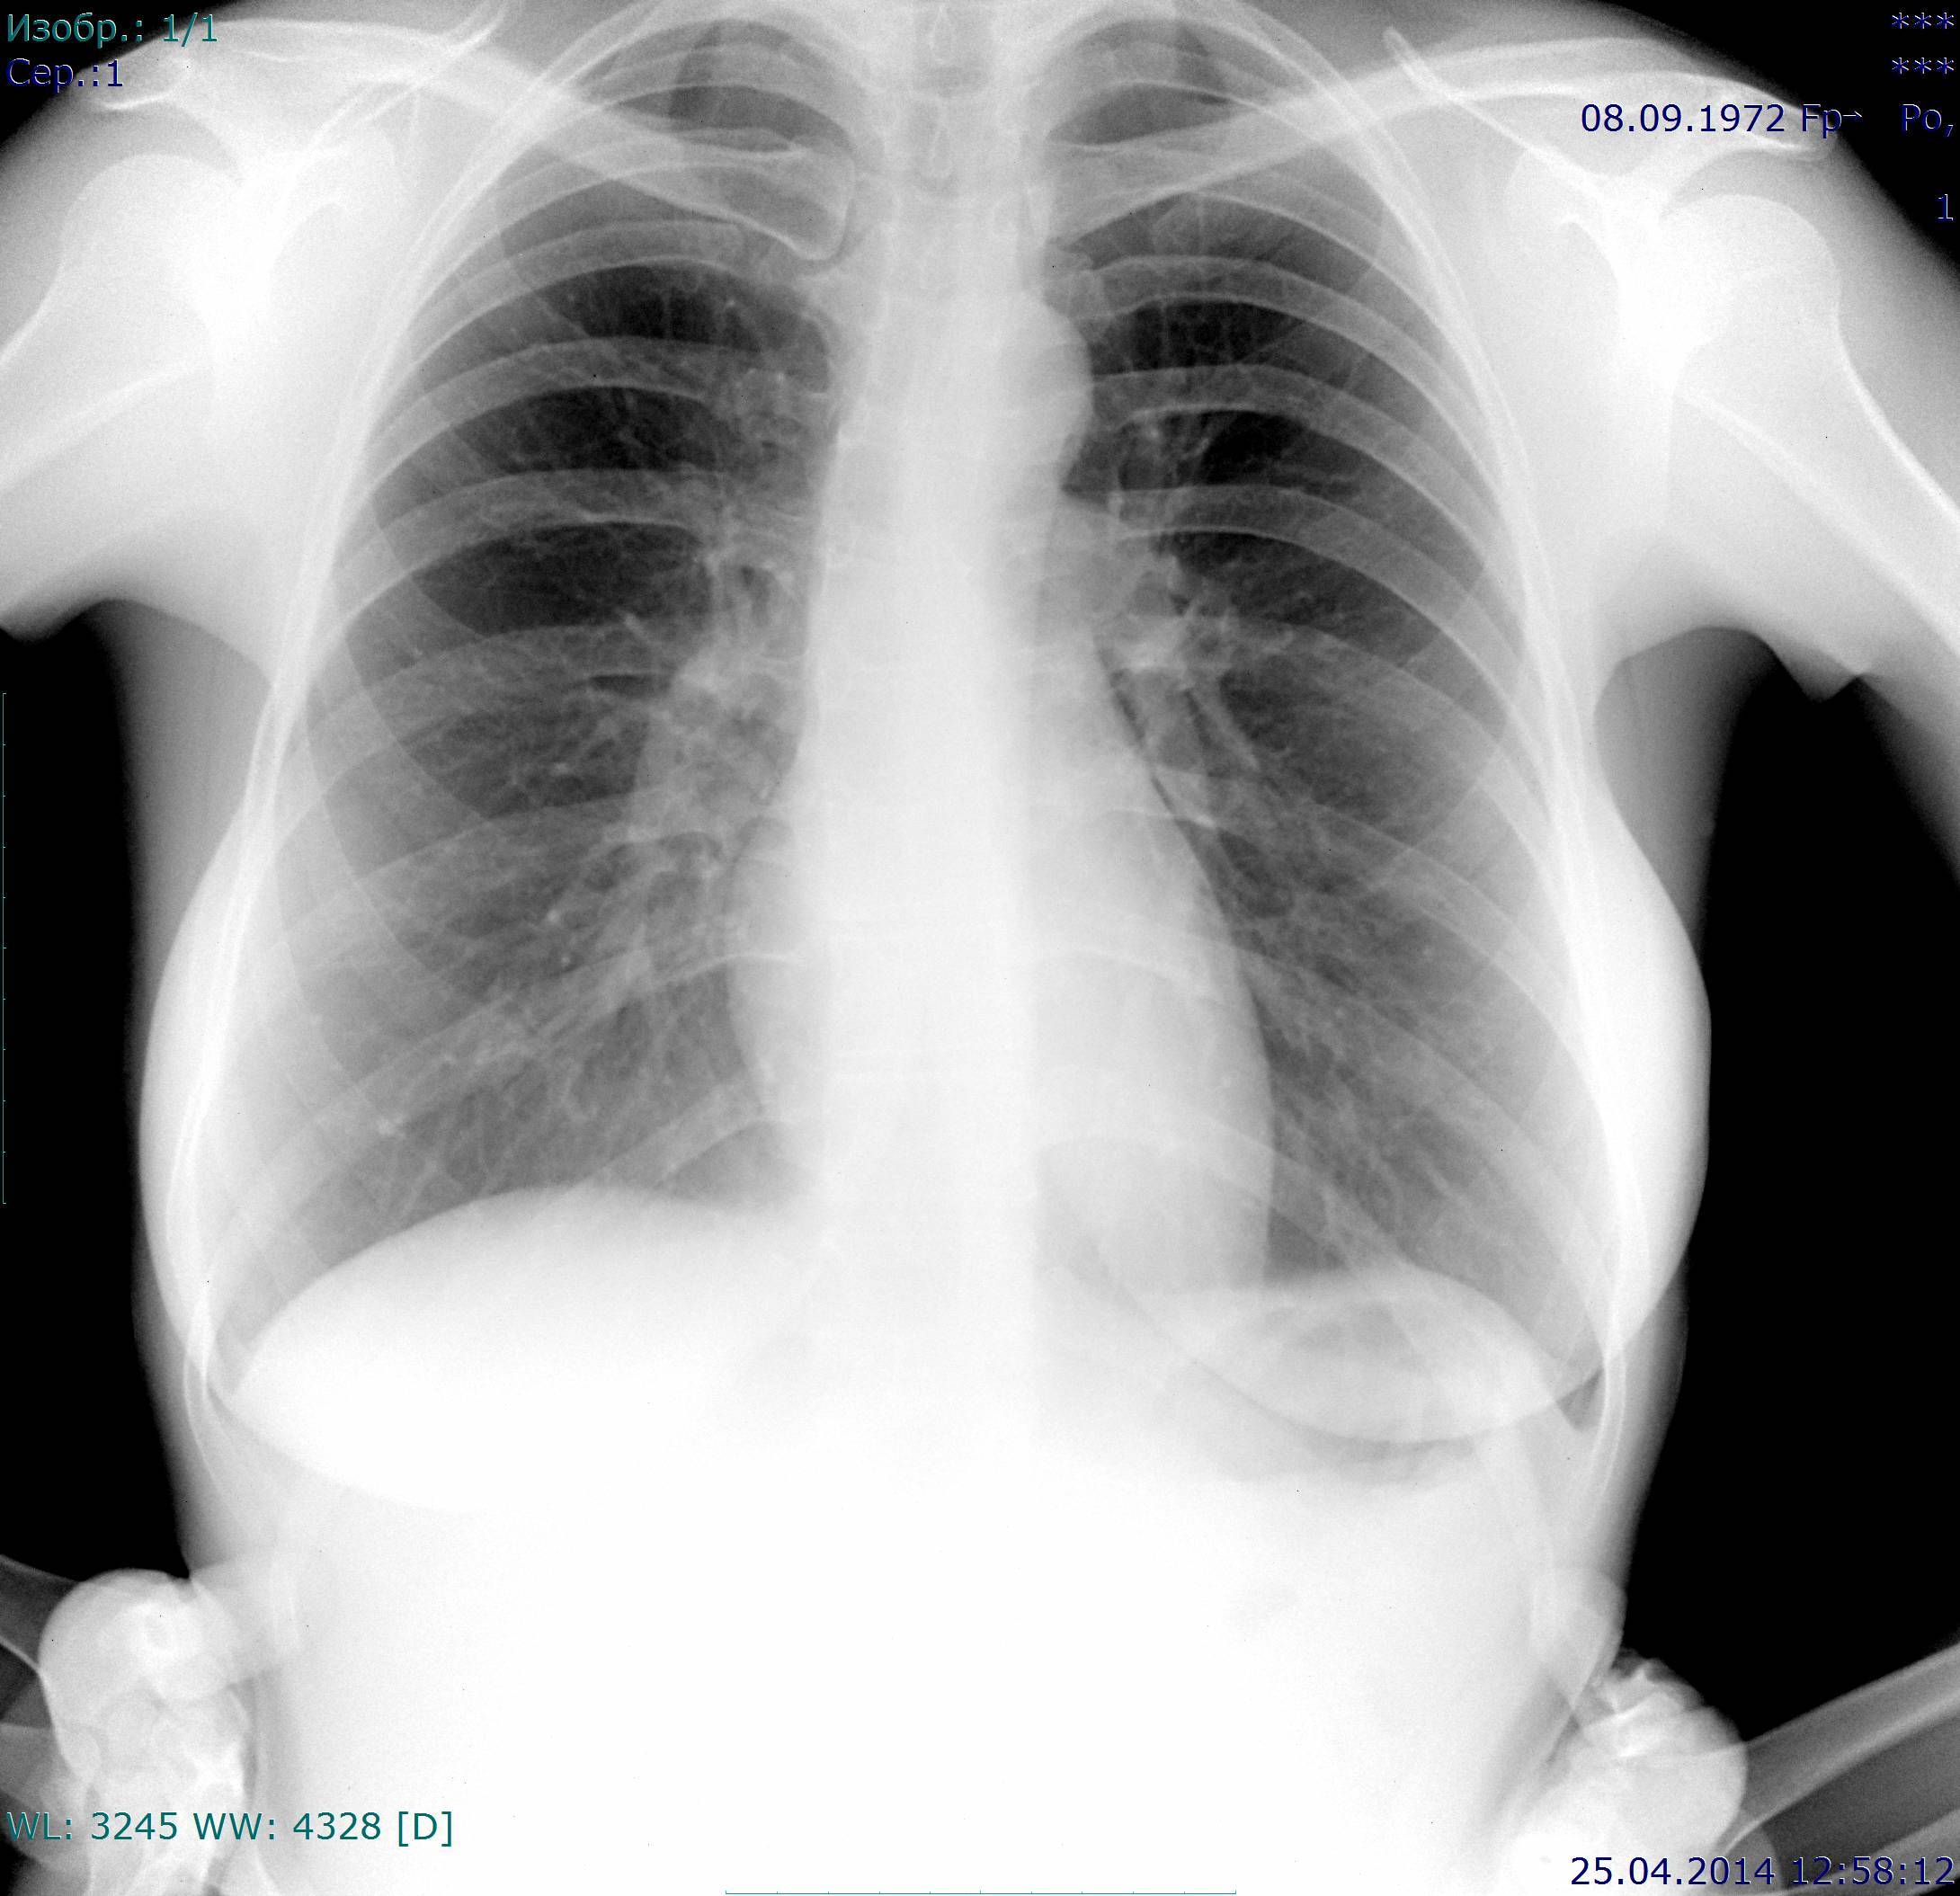

На архивных снимках этой тени нет.

Пересняли

Теперь ничего криминального не вижу. Пусть живёт долго и счастливо!

На втором снимке, в отличие от первого, задний отрезок 4-го ребра справа расположен выше ключицы, а на первом снимке - на ключице. На втором снимке наружные синусы больше прикрыты тенями молочных желез, на первом снимке - меньше. Значит центральный луч при съёмке во втором случае располагался выше, чем в первом случае, и видимая на первом снимке тень на втором сместилась книзу. Потеряла четкость, располагается там же, на 6-м ребре, но ниже. И все равно линия сосудистого рисунка здесь как бы замыкает овал.